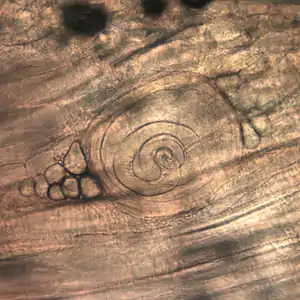

Trichinella larvae in pressed bear meat, partially digested with pepsin. The classic coil shape is visible.